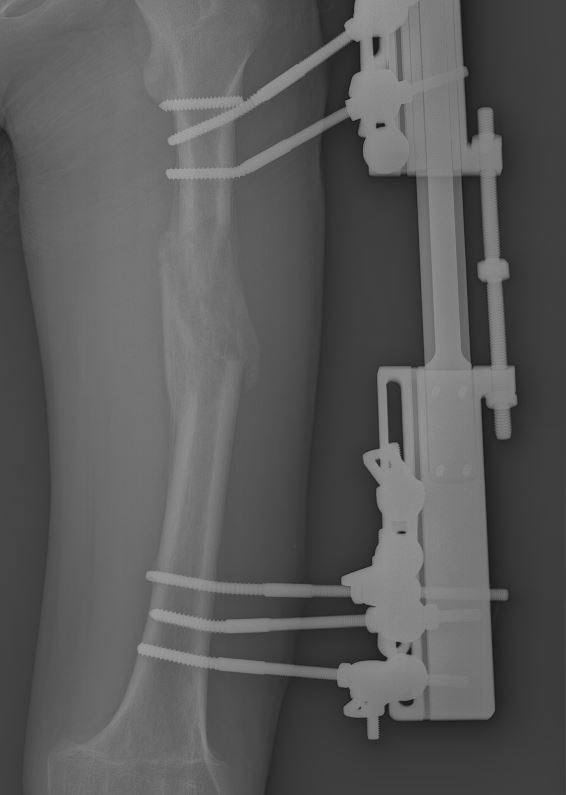

16-летней Матвей из Подмосковья (имя изменено) пять лет назад получил серьёзную травму, после чего одна из ног перестала расти — за эти годы она стала короче другой на 6 сантиметров. В этом году врачи стали это исправлять. «В апреле специалисты нашей больницы наложили стержневой дистракционный аппарат и сделали остеотомию бедренной кости, то есть мы пересекли кость и при помощи специального аппарата постепенно сформировали в промежутке костный регенерат для удлинения конечности», — рассказал главврач МОДКТОБ Александр Григорьев.

Матвею предстояло полгода ходить с аппаратом на ноге и восстанавливаться. На пятый месяц парень решил погонять на самокате и упал — перелом фиксирующего стержня, новая операция на ногу. «Спустя 5 месяцев, когда пациент уже был близок к выздоровлению, травмы повернули время назад. Пришлось выполнить демонтаж аппарата, к счастью, разница в длине скомпенсирована. Молодому человеку наложили гипсовую повязку до полного восстановления кости», — добавил врач.